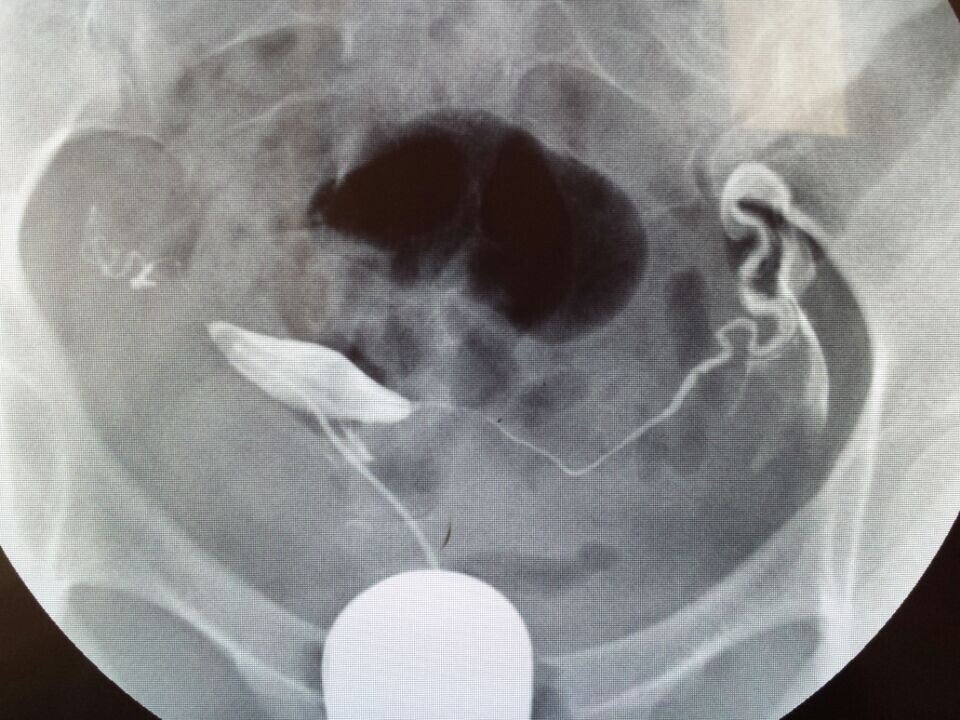

求医生帮我看一下输卵管造影的片子,在当地的妇婴医院造影后,医生太忙,没有给仔细讲解,希望专家帮我看下该采用什么方案,是否严重,如何治疗,跪谢!~有慢性阑尾炎病史,月经周期一直不准,40-50天左右来一次月经,雌激素比较低,一直在喝中药调理月经。备孕6个月监测排卵但是一直没有怀孕,这个月初做了碘油输卵管造影,当时患者太多,大夫没有做过多讲解,就给开了两盒治疗盆腔炎的药,也没有告诉用不用挂吊瓶消炎,现在造影后一个星期了,右侧输卵管部位每天都会隐隐的疼,是否该需要输液呢?